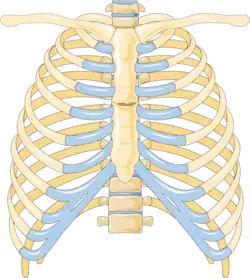

Sternal fracture

A sternal fracture is a fracture of the sternum (the breastbone), located in the center of the chest. The injury, which occurs in 5–8% of people who experience significant blunt chest trauma, may occur in vehicle accidents, when the still-moving chest strikes a steering wheel or dashboard[1] or is injured by a seatbelt. Cardiopulmonary resuscitation (CPR), has also been known to cause thoracic injury, including sternum and rib fractures. Sternal fractures may also occur as a pathological fracture, in people who have weakened bone in their sternum, due to another disease process.[2] Sternal fracture can interfere with breathing by making it more painful; however, its primary significance is that it can indicate the presence of serious associated internal injuries, especially to the heart and lungs.[3]